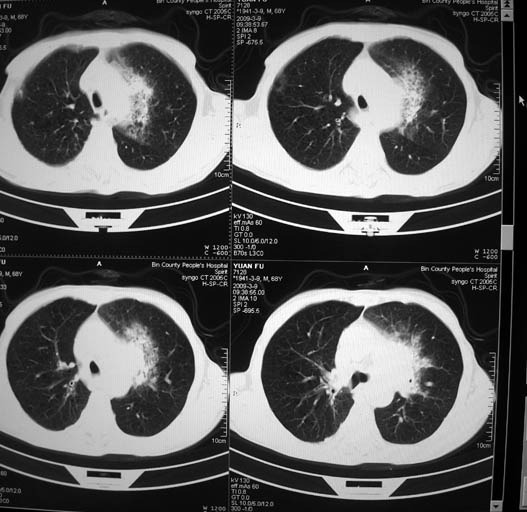

男,68岁,左上肺占位,肺门淋巴结转移?

支持楼主!(左上肺周围性肺癌伴纵隔淋巴结转移)

1)考虑左肺上叶尖段周围型肺癌并阻塞性肺炎,纵隔淋巴结转移。2)心包少量积液。

支持楼主!(左上肺周围性肺癌并阻塞性肺炎、纵隔淋巴结转移)

考虑左肺上叶尖段周围型肺癌并阻塞性肺炎,纵隔淋巴结转移.

考虑两肺播散性肺结核